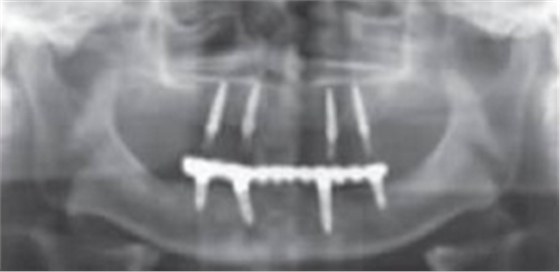

術(shù)后曲面斷層全景片(圖19)可見種植體在上頜位置較為理想,同時(shí)可見臨時(shí)義齒種植體開孔位置在13、23舌側(cè)、16、26牙合面近中,上下頜咬合關(guān)系理想。患者對(duì)種植臨時(shí)修復(fù)義齒滿意。

圖19 即刻修復(fù)后全景片